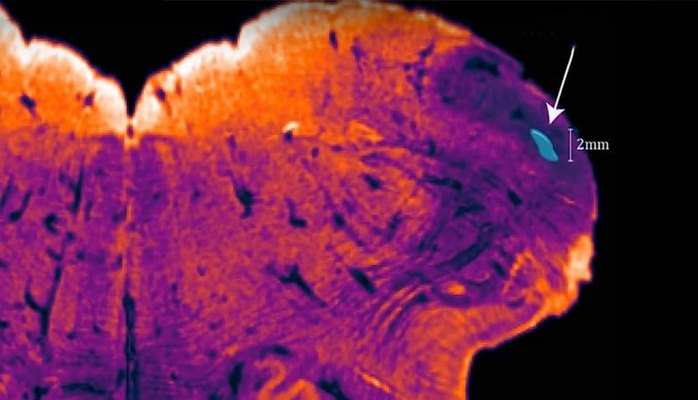

НАУКА Ученые раскрыли необычную связь между астмой и ожирением 26 November 2018, 14.30 НАУКА Ученые нашли способ превращать углекислый газ в пластмассы и ткани 26 November 2018, 14.16 НАУКА Ученые ищут способ заменить собак «Электронным носом» 26 November 2018, 14.07 НАУКА Можно ли жить вверх тормашками? 26 November 2018, 12.06 НАУКА Как мозг предсказывает будущее 26 November 2018, 10.32 НАУКА Найден новый способ сохранения урожайности для разных стран 26 November 2018, 10.31 НАУКА Впервые охарактеризована архитектура генома птиц 26 November 2018, 10.28 НАУКА Ученые изобрели подводного прыгающего робота 25 November 2018, 17.20 НАУКА Первый в мире сканер для всего тела: как это работает 25 November 2018, 16.44 НАУКА Обнаружен ранее неизвестный участок мозга 25 November 2018, 15.17 НАУКА Учёный: Путешествия во времени могут стать реальностью 25 November 2018, 15.04 НАУКА Невероятное обезболивающее из самого острого вещества в мире 25 November 2018, 14.55 «30313233 34(current)35363738»